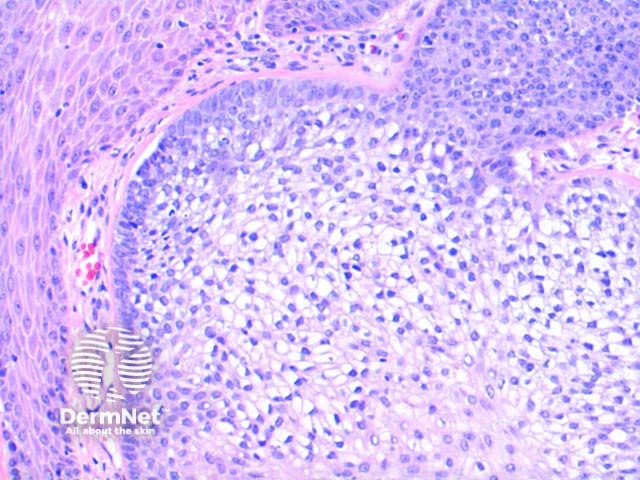

Trichilemmoma is usually a symmetrical epithelial nodular proliferation. Figure 1. There may be mild papillomatosis with overlying hyperkeratosis. Figure 2. The key finding is of a downgrowth of epithelial cells with increasing clear cell differentiation. Figure 2, Figure 3. These changes are frequently more obvious towards the base of the lesion. The clear cell is PAS positive but diastase labile indicative of the glycogen contents. There is often basal peripheral palisading, resting on a distinctive PASD positive eosinophilic hyaline basement membrane. Figure 4.

Figure 3